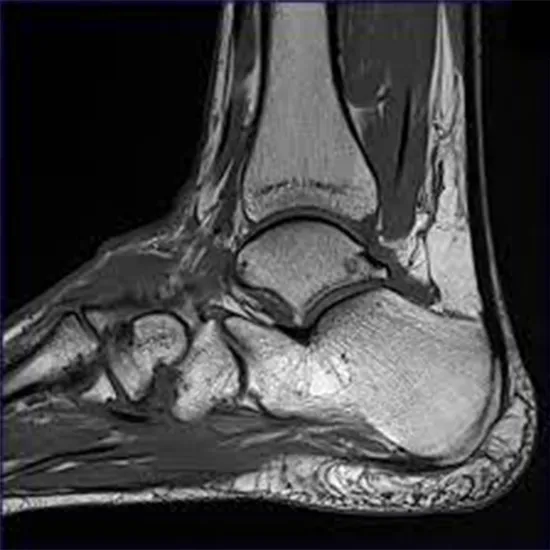

The extremities MRI is a form of scan that is performed to diagnose problems with the arm, leg, hand, or foot.

It helps to diagnose the abnormalities of the bones, joints, nerves, and other areas around them to get them treated on time.

Highly sensitive scanner captures cross-section pictures of the interior of the extremities using radio waves and a magnetic field to identify abnormalities in the muscles, joints, bones, nerves, and blood vessels.